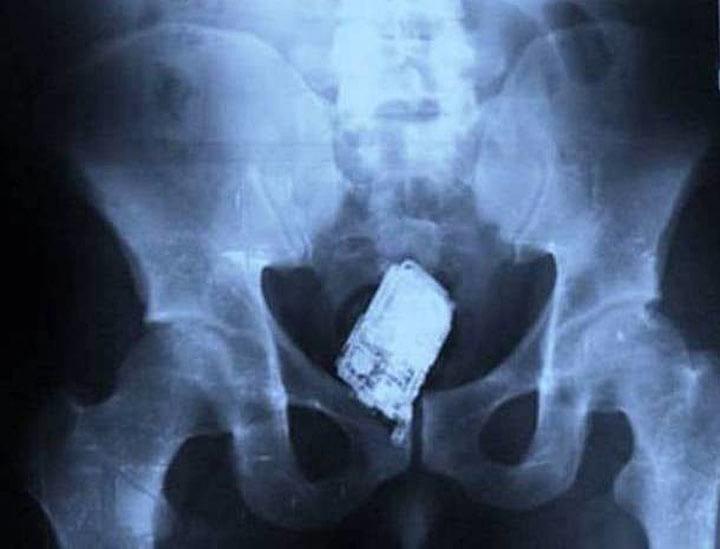

6. А это — попытка контрабанды мобильного телефона